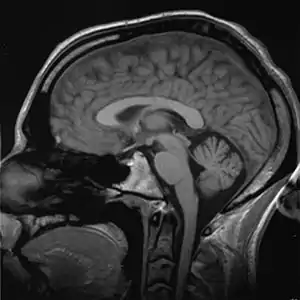

دماغ

الدماغ هو عضو يعمل كمركز للجهاز العصبي في جميع الفقاريات ومعظم اللافقاريات.[2] يقع في الرأس، يكون قريبًا من الأعضاء الحسية للحواس مثل الرؤية. وهو العضو الأكثر تعقيدًا في جسم الفقاريات. في الإنسان ، تحتوي القشرة المخية على ما يقرب من 14-16 مليار خلية عصبية،[3] ويقدر العدد التقديري للخلايا العصبية في المخيخ بـ 55-70 مليار.[4] كلّ خلية عصبيّة مرتبطة بواسطة السنابس إلى عدّة بالآلاف الخلايا العصبيّة الأخرى. تتواصل هذه الخلايا العصبية في ما بعضها عن طريق ألياف طويلة تسمى المحاور.

أبسط طريقة للحصول على معلومات حول تشريح الدماغ هي عن طريق الفحص البصري، ولكن تطوير العديد من التقنيات الأكثر تعقيدًا مازال مستمرًا. أنسجة الدماغ في حالتها الطبيعية لينة جدًا بحيث لا يمكن التعامل معها، ولكن يمكن تقويتها عن طريق وضعها في الكحول أو غيرها من المثبتات، ومن ثم تقطيعها إلى شرائح لفحص الأجزاء الداخلية بصريًا. يتكون الجزء الداخلي من الدماغ من مناطق تسمى المادة الرمادية ذات اللون داكن، مفصولة عن منطقة المادة البيضاء ذات لون أفتح. ويمكن الحصول على المزيد من المعلومات عن طريق تلطيخ شرائح من أنسجة المخ بمجموعة متنوعة من المواد الكيميائية التي تبرز المناطق التي توجد فيها أنواع محددة من الجزيئات بتركيزات عالية. من الممكن أيضًا فحص البنية المجهرية لأنسجة الدماغ باستخدام المجهر، وتتبع نمط الاتصالات من منطقة دماغية إلى أخرى.[9]